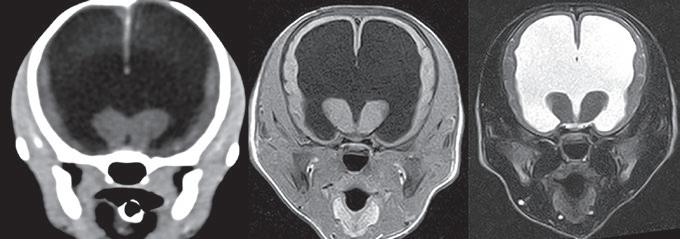

Agujas de acceso vascular